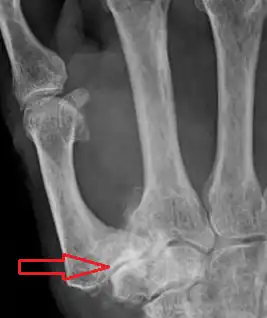

Classification

TMC OA severity was classified by Eaton and Littler which can be simplified as follows:[17][18]

Stage 1:

• slight widening of the joint space

• < 1/3 subluxation of the joint (in any projection)

Stage 2:

• Osteophytes, < 2 mm in diameter, are present. (usually adjacent to the volar or dorsal facets of the trapezium)

Stage 3:

• Osteophytes, > 2 mm in diameter, are present (usually adjacent to the volar and dorsal facets of the trapezium)

• Slight joint space narrowing

Stage 4 trapeziometacarpal osteoarthritis, with major subluxation of the joint

Stage 4:

• Narrow joint space

• Concomitant scaphotrapezial arthritis

A simpler classification is no arthritis, some arthritis, and severe arthritis.[19] This simpler classification system omits the potentially contradictory details of the Eaton/Littler classification and keeps scaphotrapezial arthrosis separate.